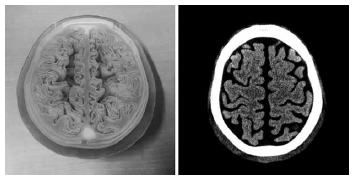

図5に、頭部CTのためのファントムを示す。このファントムでは3次元方向の立体的な脳構造までモデリングして造形しており、骨直下に生じるビームハードニングアーチファクトに対するコーン角の影響などを評価するために用いた。

a ファントムの外観

b CT画像